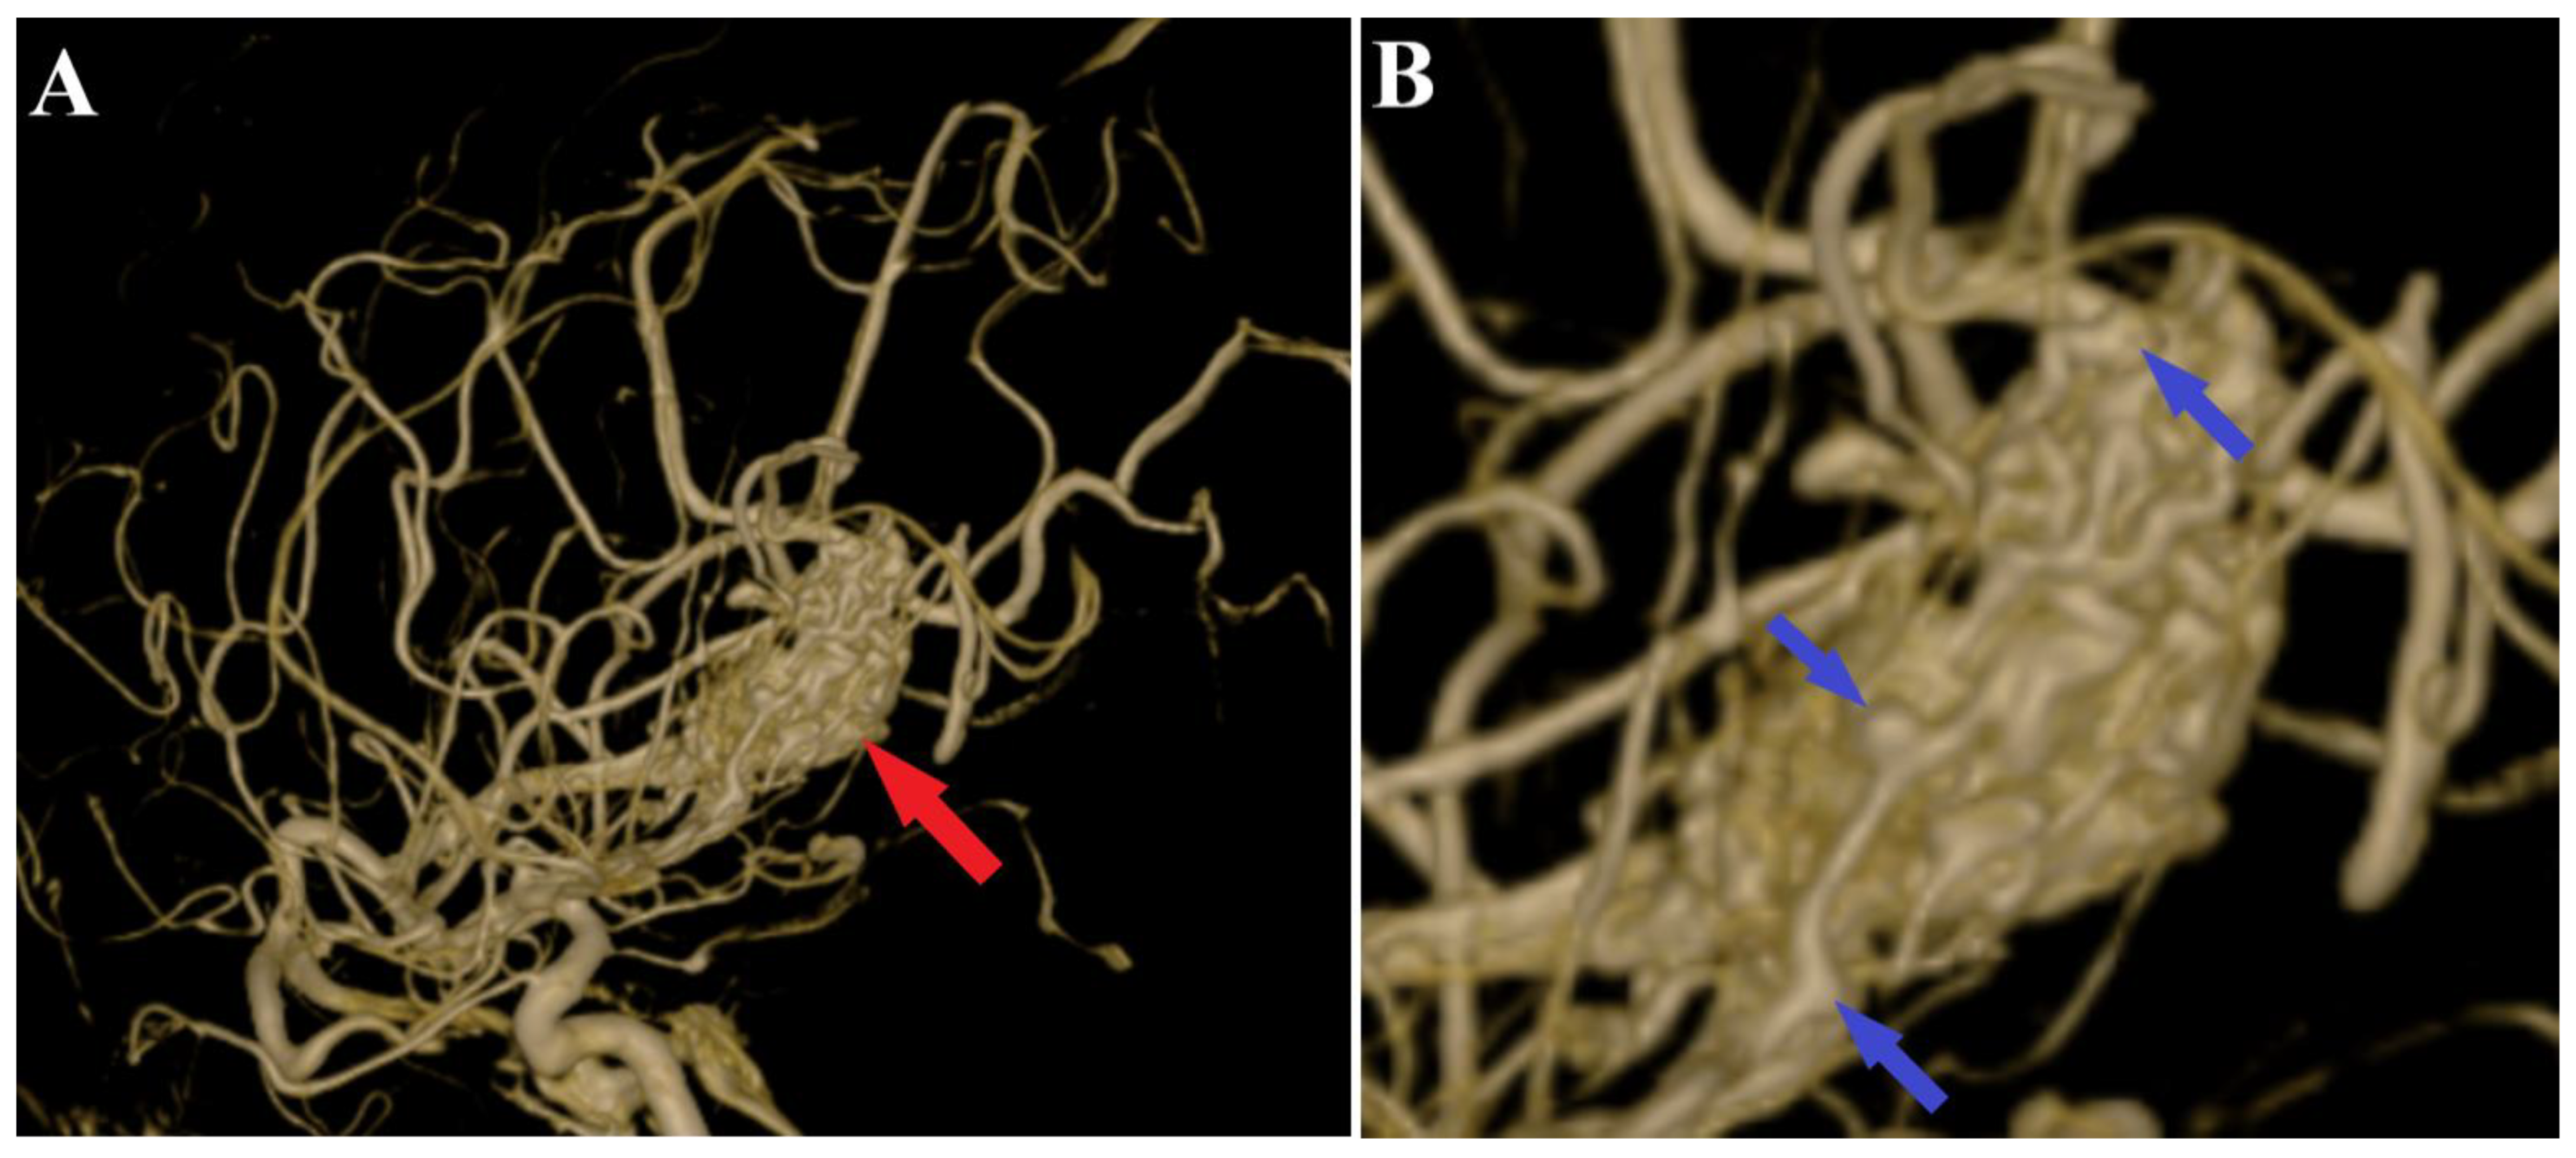

Figure 3.

Preoperative 3D DSA rotational angiography. The 3D reconstruction of rotational DSA (A) depicts the tridimensional topography of the arteriovenous malformation (red arrows). In high-resolution image (B), multiple intranidal sacullar and fusiform aneurysms were found (blue arrows).